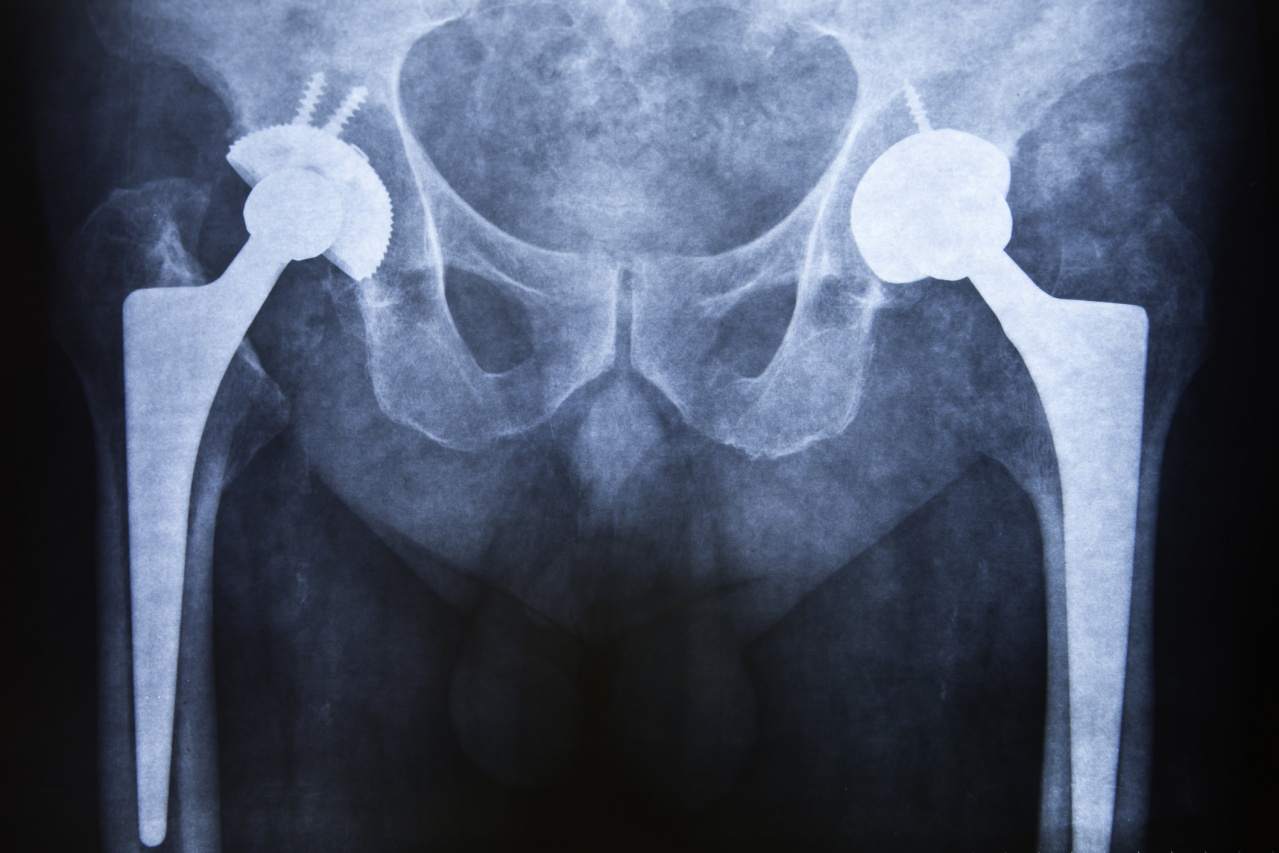

Dolegliwości związane ze stawami biodrowymi i kolanowymi mają często przewlekły charakter i wymagają długoterminowej opieki medycznej. W gabinecie ortopedyczno-urazowym lekarz diagnozuje między innymi:

W przypadku pacjentów z zaawansowaną chorobą zwyrodnieniową lekarz kwalifikuje do zabiegów endoprotezoplastyki kolan i bioder.